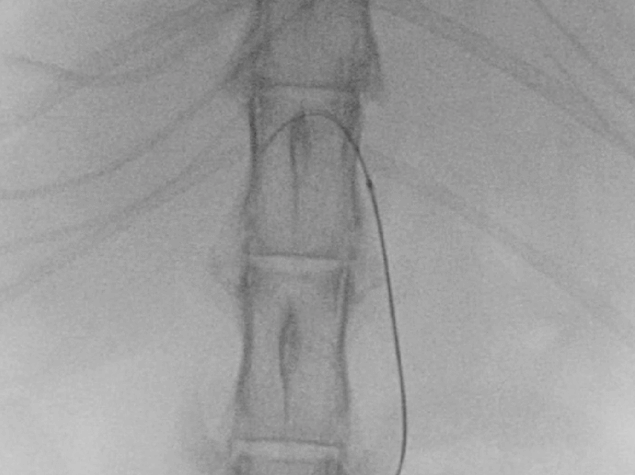

オーナーと相談の結果、まずは腫瘤からの出血の制御を目的として第3病日にTAE(*)を実施する事となった。

(*)TAE

Cios Fusion(SIEMENS)

4Fr RADIFOCUS INTRODUCER(TERUMO)

4.2Fr RIM-S型 catheter(Hanako Medical)

1.7Fr Estream micro catheter(東レ)

0.035inch RADIFOCUS GUIDE WIRE M(TERUMO)

0.014inch Cross Winder(東レ)

ジェルパート(日本化薬)

TAE

腹腔動脈選択~腹腔動脈造影

総肝動脈選択~feeder選択

塞栓剤注入

ジェルパート1mm 粒(日本化薬)